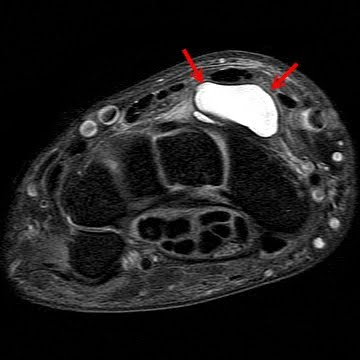

Sometimes the surgeon will shine a light through the cyst or remove a small amount of fluid from the cyst for evaluation. Your doctor may take an x-ray, and in some cases additional imaging studies (MRI) and ana a possible biopsy may be ordered.

X-Ray MRI